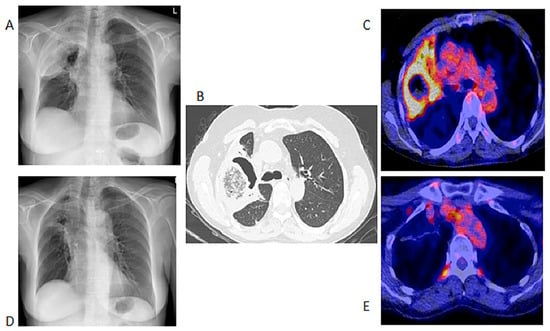

In the 32 patients that had repeated [18F]FDG PET/CT imaging to assess the responses, the follow-up helped the clinicians to decide to stop, continue or change antifungal therapy (Figure 3). [18F]FDG PET/CT detected previously unknown IFI lesions in five patients of the 18 that were referred for the staging of the infection, which led to therapy prolongation in four and a change in therapy in one. In the 10 patients with indications of unexplained fevers or increasing infective markers, [18F]FDG PET/CT was found to be useful in four patients, as it guided the biopsy that led to the diagnosis of the IFI (see Figure 4). In the seven patients that were being prepared for ASCT, [18F]FDG PET/CT was considered to add value for all. In four patients, the [18F]FDG PET/CT allowed clinicians to proceed with the procedure; in two others, further antifungal therapy was provided with follow-up with [18F]FDG PET/CT, and a biopsy was conducted in one of the patients before ASCT was performed. Finally, in the six patients where scans was performed to assess metabolic activity in residual anatomic lesions, [18F]FDG PET/CT was considered useful. There was a complete metabolic response in five patients, and in two patients, further antifungal treatment was instituted. Table 5 tabulates the patients for which [18F]FDG PET/CT was deemed to have added value. Figure 4 shows a female patient with acute myeloid leukemia while on antifungal therapy, where [18F]FDG PET/CT explained the increasing infective markers by demonstrating multiple IFI lesions outside the thorax.

Figure 4. Sixty-three-year-old female with acute myeloid leukemia on treatment for pulmonary aspergillosis. [18F]FDG PET/CT was performed because there was unexplained fever, and the IFI lesions seen on HR CT (A) were similar to in the HR CT scan performed a month and 2 months earlier. [18F]FDG PET/CT scan (B) showed multiple IFI lesions outside the thorax, providing an explanation for the persistent fever.